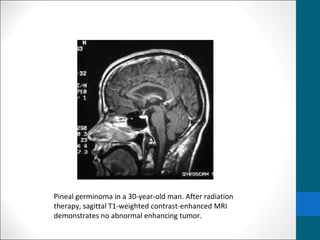

Pineal germinoma in a 30-year-old man. After radiation

therapy, sagittal T1-weighted contrast-enhanced MRI

demonstrates no abnormal enhancing tumor.

Pineal germinoma ina 30-year-old man. After radiation therapy, sagittal T1-weighted contrast-enhanced MRI demonstrates no abnormal enhancing tumor.